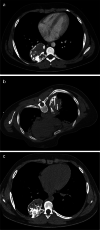

Materials and methods: We collected data of children with thoracic mesenchymal hamartomas who were treated at our institution from 2005 to 2020 using various percutaneous techniques. Techniques included radiofrequency thermoablation, microwave thermoablation (microwave thermoablation) and cryoablation.

Results: Five children were treated for chest wall hamartomas; one child showed bilateral localization of the mass. Two children underwent microwave thermoablation, one radiofrequency thermoablation and two cryoablation; one child treated with cryoablation also had radiofrequency thermoablation because mass volume increased after the cryoablation procedure. The median reduction of tumor volume was 69.6% (24.0-96.5%). One child treated with microwave thermoablation showed volumetric increase of the mass and underwent surgical removal of the tumor. No major complication was reported.